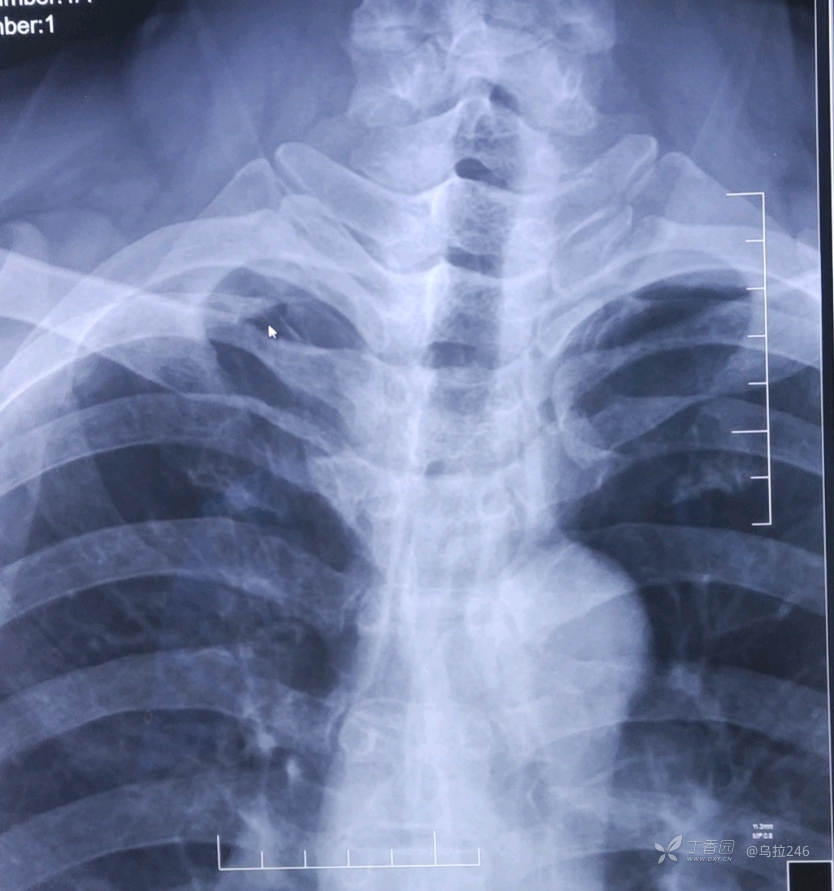

感觉平片真的很难写,以为体检病人右肺尖发现有斑片状密度增高影,报了纤维化病变,或继发型肺tb可疑,后面来做了ct,不是tb。想请各位老师指导一下,如何在平片上区分tb和普通的炎性病变呢?